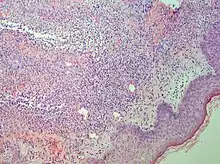

Sweet syndrome lesions with the classical form of the dermatosis. | |

There is an elevated white blood cell count. There is infiltrates by neutrophil granulocytes on histologic examination.

Studies show a moderate neutrophilia (less than 50%), elevated ESR (greater than 30 mm/h) (90%), and a slight increase in alkaline phosphatase (83%). Skin biopsy shows a papillary and mid-dermal mixed infiltrate of polymorphonuclear leukocytes with nuclear fragmentation and histiocytic cells. The infiltrate is predominantly perivascular with endothelial-cell swelling in some vessels, but vasculitic changes (blood clots; deposition of fibrin, complement, or immunoglobulins within the vessel walls; red blood cell extravasation;inflammatory infiltration of vascular walls) are absent in early lesions.Perivasculitis occurs secondarily, because of cytokines released by the lesional neutrophils. True transmural vasculitis is not an expected finding histopathologically in SS.